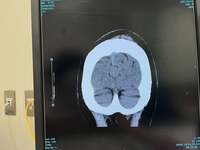

続けて「頭を打ったので、夫が心配していろいろ電話して、近くの脳神経外科を探して、やっとCTを撮影してもらいました」と検査を受けたことを報告。「幸い、今のところ脳には問題なさそうなので、一安心です」と検査結果を明かし、腕にできた傷については「家に帰って水道水で血液を洗い流し、キズパワーパッドを貼り付けました」と説明した。